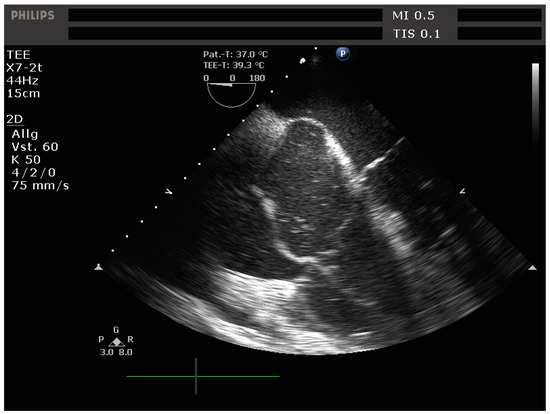

- Signs of RV dilation: D-shaping, increased RV:LV ratio, tricuspid regurgitation

- Signs of impaired RV systolic function: reduced tricuspid annular plane systolic excursion (TAPSE)

- Signs of elevated RV preload (plethoric inferior vena cava [IVC])